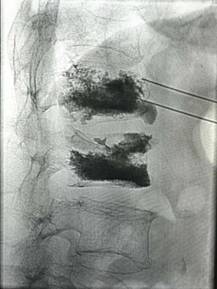

经皮穿刺椎体成形术

优点:微创,迅速解决老年骨质疏松性骨质疼痛。

经皮椎体成形术(PKP、PVP)治疗老年骨质疏松性骨折

优点:损伤小、见效快、安全性高。可以早期下床。